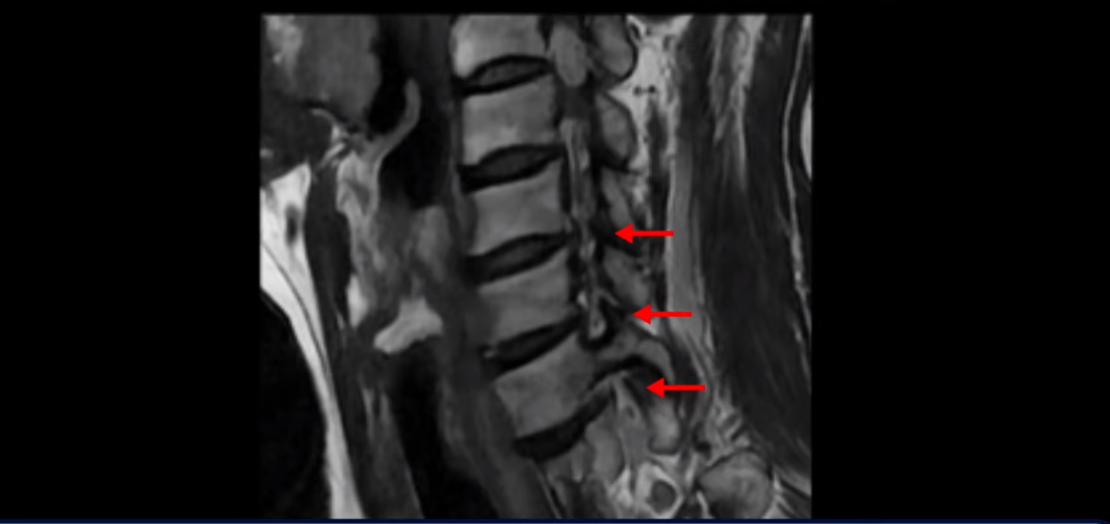

이분 MRI를 보면 세 마디의 퇴행성 목디스크가 있습니다. 4번 5번, 5번 6번과 6번 7번이 세 마디인데

그런데 이 환자분의 방사통은 왼쪽 어깨와 팔입니다. 그래서 이 4번 5번 디스크 파열은 왼쪽 방사통의 원인이 아닌 걸로 보입니다. 6번 7번을 보면 디스크가 왼쪽으로 밀려 나와 있고, 뼈도 자라나 있습니다.

이렇게 뼈가 자라나 있으니까, 신경가지가 빠져나가는 추간공을 보면 여러 마디가 다 좁아져 있습니다.

이런 걸 협착이라고 합니다. 목이 협착이 진행된 것이죠. 그런데 왜 목디스크, 목 협착 치료가 허리보다 훨씬 더 쉽고 빠르다고 하는 걸까요? 그 이유는 목은 하중을 허리보다 훨씬 더 적게 받기 때문입니다. 하중을 적게 받으니까 신경 눌림이 조금만 줄어도 증상이 훨씬 더 빠르게 좋아지는 것입니다.